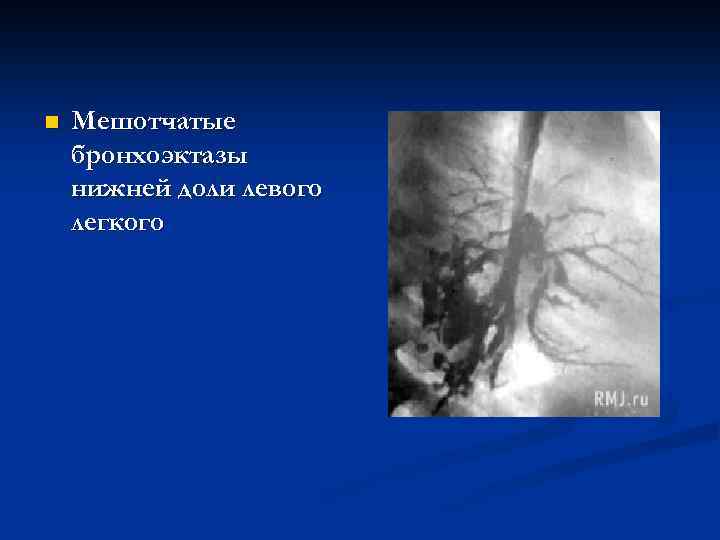

n Мешотчатые бронхоэктазы нижней доли левого легкого